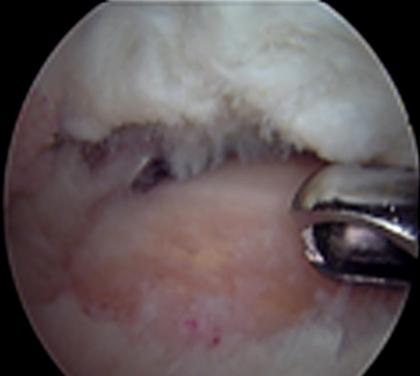

การรักษาโดยการผ่าตัดผ่านกล้องไหล่ ถือเป็นมาตรฐานการรักษาโรคของข้อไหล่ที่ยอมรับกันทั่วโลก นอกจากสามารถให้การวินิจฉัยแล้วยังเป็นการรักษาในคราวเดียวกัน กรณีที่เหมาะสมต่อการผ่าตัดส่องกล้องข้อไหล่ คือโรคของข้อไหล่ที่รักษาด้วยวิธีอนุรักษ์นิยมอย่างเต็มที่แล้ว ซึ่งประกอบด้วย การรับประทานยาแก้ปวด เช่น พาราเซตามอล, ยาลดอาการอักเสบที่ไม่ใช่สเตียรอยด์ และยาคลายกล้ามเนื้อ ร่วมกับกายภาพบำบัดอย่างเต็มที่แล้วไม่ได้ผล เป็นเวลาอย่างน้อย 3-6 เดือน จึงพิจารณานำวีธีการผ่าตัดผ่านกล้องมารักษา ซึ่งจะทำการเปิดแผลขนาด 0.5 - 1 ซ.ม. ประมาณ 2-3 แผล เพื่อใส่กล้องขนาดประมาณ 4 มิลลิเมตร ใส่น้ำเกลือเข้าไปในข้อเพื่อขยายพื้นที่ในการผ่าตัด และใส่อุปกรณ์การผ่าตัดเพื่อทำการรักษา พบว่าผลการรักษาไม่แตกต่างจากการรักษาโดยการเปิดแผล แต่กลับฟื้นตัวได้เร็วขึ้น

ตัวอย่างการผ่าตัดผ่านกล้องรักษากระดูกงอกทับเส้นเอ็นหัวไหล่